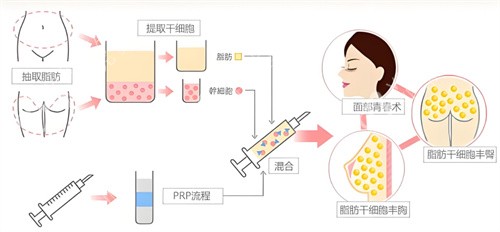

自体脂肪隆胸手术完成两年后,移植的脂肪已经基本稳定,但这不意味着可以完全放松警惕。本文将为您详细介绍术后两年的注意事项、潜在风险以及如何通过科学护理维持理想结果。

在良好护理下,自体脂肪隆胸结果通常可长期维持。结果维持时间受个人体质、医生技术、术后护理等多种因素影响。

保持稳定体重、良好生活习惯和定期乳腺检查,是长期维持满意结果的关键。